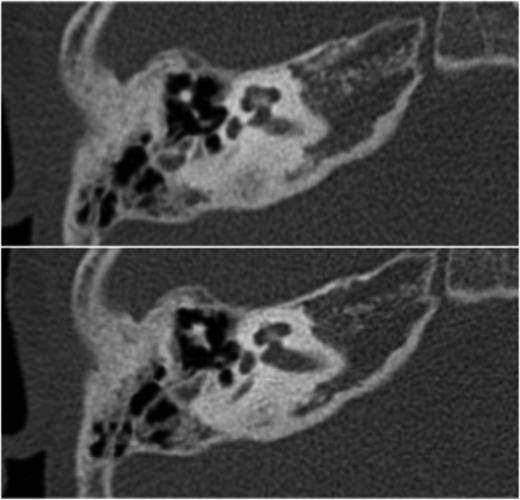

At this stage, a computed tomography (CT) scan of the temporal bone was undertaken. The stapes was maloriented on the oval window; however, the other ossicles appeared normal (see Figs 1 and 2). There was no middle ear effusion at the time of the CT scan.

Transverse high-resolution CT demonstrates intact ossicles with malposition of the stapes